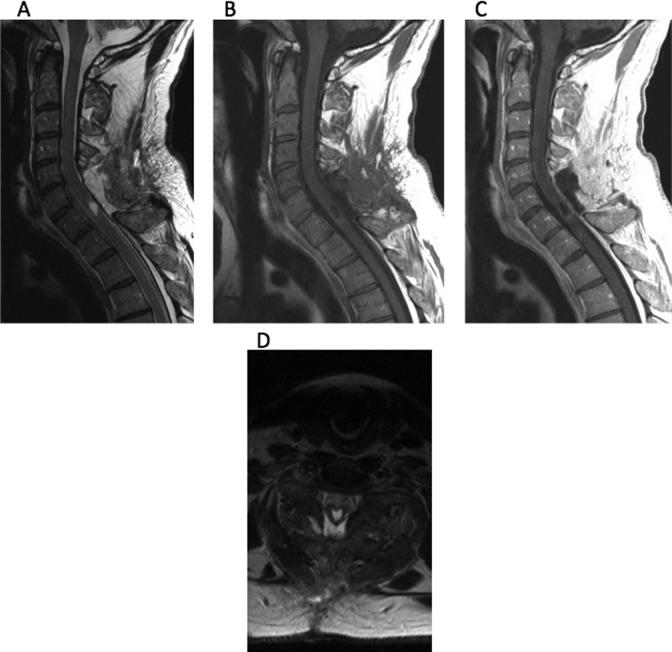

脊柱手术中术中超声的应用。

Use of Intraoperative Ultrasound During Spinal Surgery.

Intraoperative ultrasound has been used by spine surgeons since the early 1980s. Since that time, more advanced modes of intraoperative imaging and navigation have become widely available. Although the use of ultrasound during spine surgery has fallen out of favor, it remains the only true real-time imaging modality that allows surgeons to visualize soft tissue anatomy instantly and continuously while operating. It is our objective to demonstrate that for this reason, ultrasound is a useful adjunctive technique for spine surgeons, especially when approaching intradural lesions or when addressing pathology in the ventral spinal canal via a posterior approach.

Surgeons should consider the use of intraoperative ultrasound when approaching intradural lesions or when addressing pathology ventral to the thecal sac via a posterior approach.

自20世纪80年代初以来,脊柱外科医生就开始使用术中超声。从那时起,更先进的术中成像和导航模式已广泛应用。尽管脊柱手术中超声的使用已不再流行,但它仍然是唯一真正的实时成像方式,使外科医生在手术过程中能够即时且持续地观察软组织解剖结构。我们的目的是证明,基于这个原因,超声对于脊柱外科医生是一种有用的辅助技术,特别是在处理硬膜内病变或通过后路处理脊髓腹侧椎管内病变时。

当处理硬膜内病变或通过后路处理硬膜囊腹侧病变时,外科医生应考虑使用术中超声。